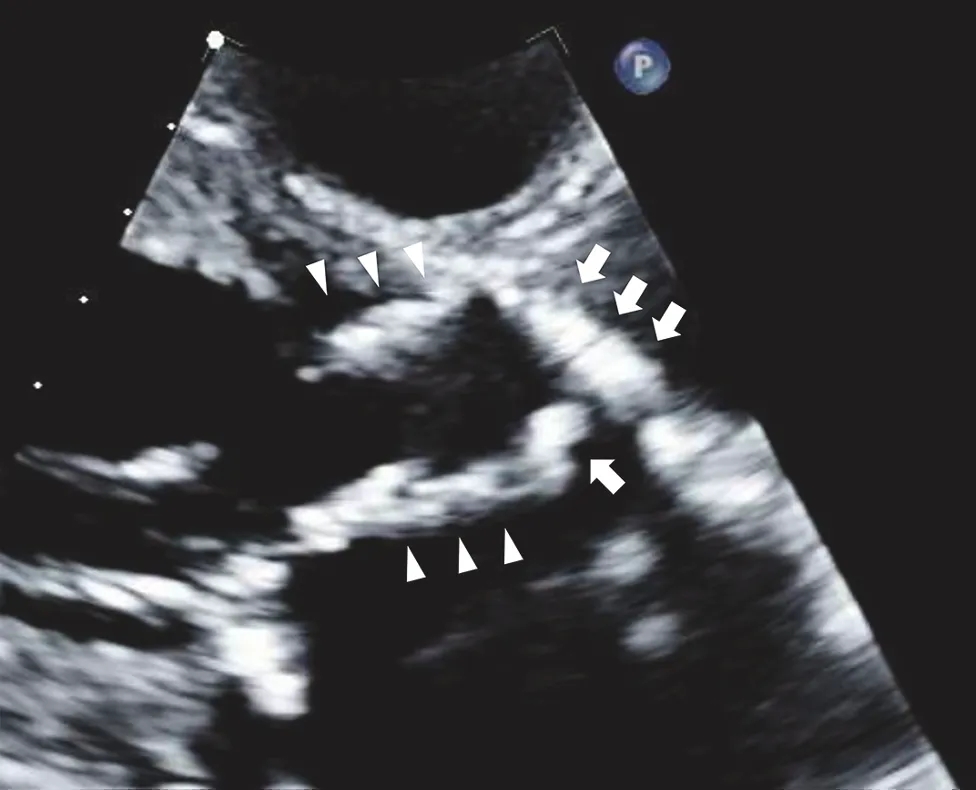

图 1经胸超声心动图显示 Evolut R 瓣膜的长轴切面

Evolut R 的瓣上瓣叶活动受限,并伴有严重的增厚和钙化(白色箭头)。瓣膜支架的心室侧也清晰可见(白色箭头)。